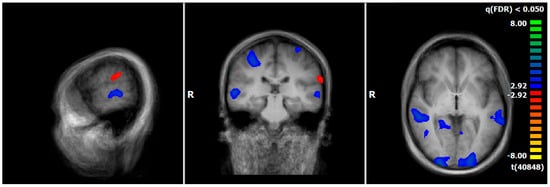

3.4. Comparison of Neuronal Responses Before and After Therapy—PPPD

3.5. Comparison of Neuronal Responses Before and After Therapy—ANX